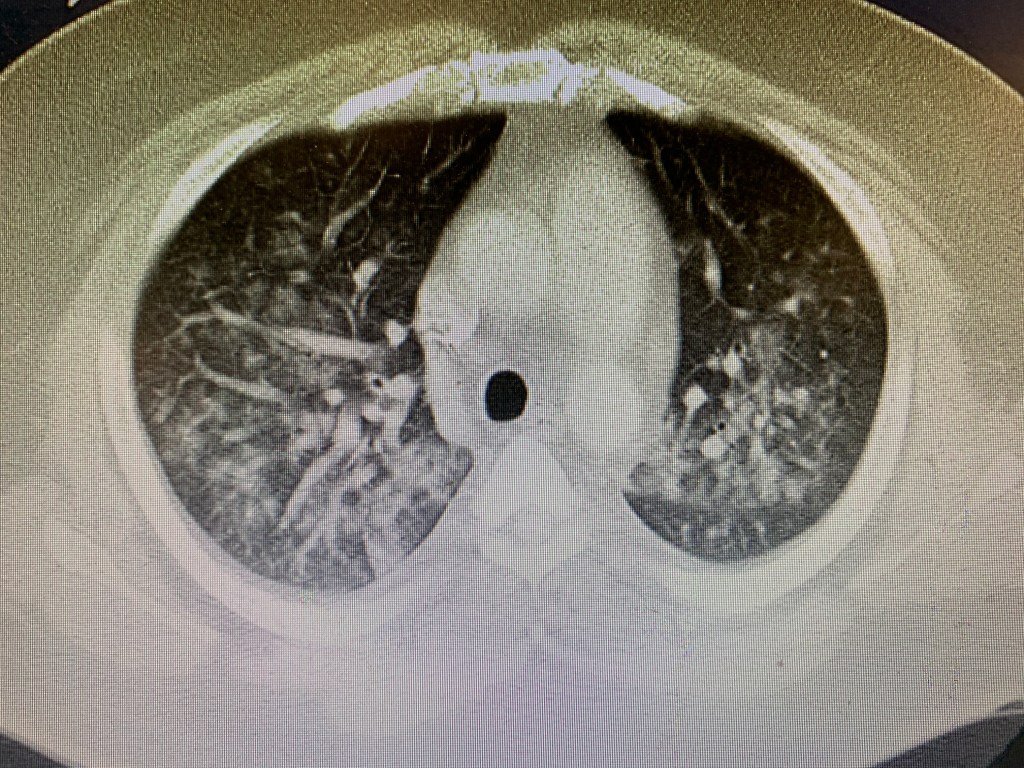

A CT is obtained:

The CT shows multifocal pulmonary infiltrates diffusely throughout the bilateral lungs. An ABG is obtained on 100% FiO2 (the patient is placed on vapotherm prior to the ABG) and the PaO2/FiO2 ratio is 150. The patient is diagnosed with ARDS and multifocal pneumonia and admitted to the ICU.

The patient had a CXR concerning for pulmonary edema (but retrospectively it was actually bilateral interstitial opacities or non cardiogenic pulmonary edema consistent with ARDS) with an echo that showed a hyperdynamic heart and a pulmonary ultrasound that showed diffuse b lines in all fields. CT confirmed the diagnosis of diffuse alveolar opacities/pneumonia. The patient did not have heart failure, but rather had sepsis secondary to pneumonia/ARDS.